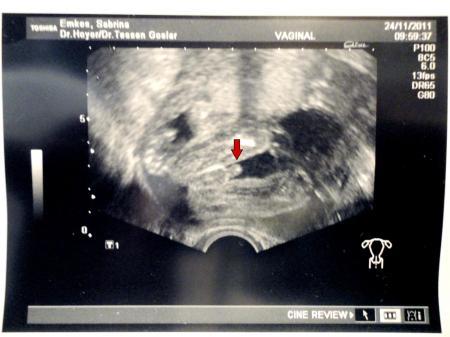

Das war mein Outing Bild...... Ein ♥♥♥Junge♥♥♥

Bild zu

miss sabrina das is ja ma megaeindeutig! so wars auch beim outing von meinem großen, das hatte auch jeder sofort sehen können.... leider hab ich nie ein outingbild bekommen....

Ja das ist wirklich eindeutig Schwiegermama die sagt schon seit Wochen das ich enen Jungen bekomme Sie hat immer gesagt meine Söhne können nur Jungs machen.....Hi Hi